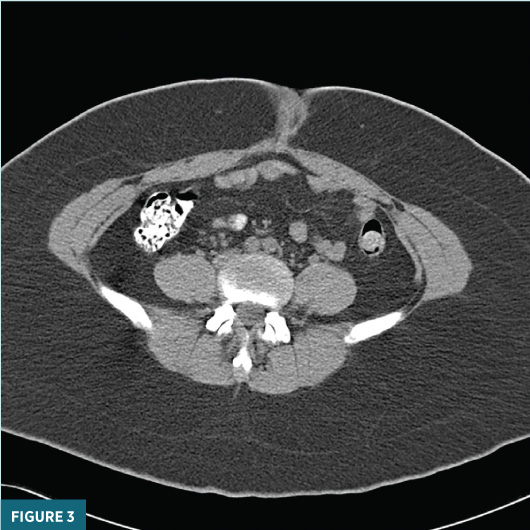

An axial unenhanced CT image at the level of the umbilicus (Figure 3) demonstrated a 3.9 cm X 3.4 cm slightly heterogenous high-attenuation umbilical lesion.